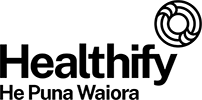

Your kidneys have a key role in your health. They filter and remove waste and excess fluid from your body. This means you need to take good care of them. Find out how to look after your kidneys, the signs they're not functioning well and more.